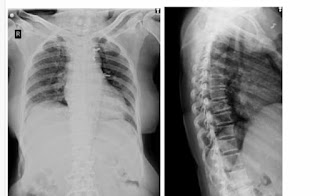

X-ray:

Mild pleural effusion and prominent right descending pulmonary artery

Cardiomegaly